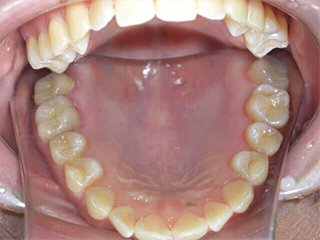

どこを治したかわかりますか?正解は、、、、、、、こうなってました。金属の詰め物、被せ物を取り、中の虫歯や金属片をきれいにし、形を整えたところです(写真は右上だけですが左上も同じようにします)。患者様が他院にて歯科治療を受け、健康保険適用の金属にて治療を終えてからもともとあったアトピー性皮膚炎が悪化し、調べたところ歯科金属アレルギーであったことが判明。当院にご相談に来られました。